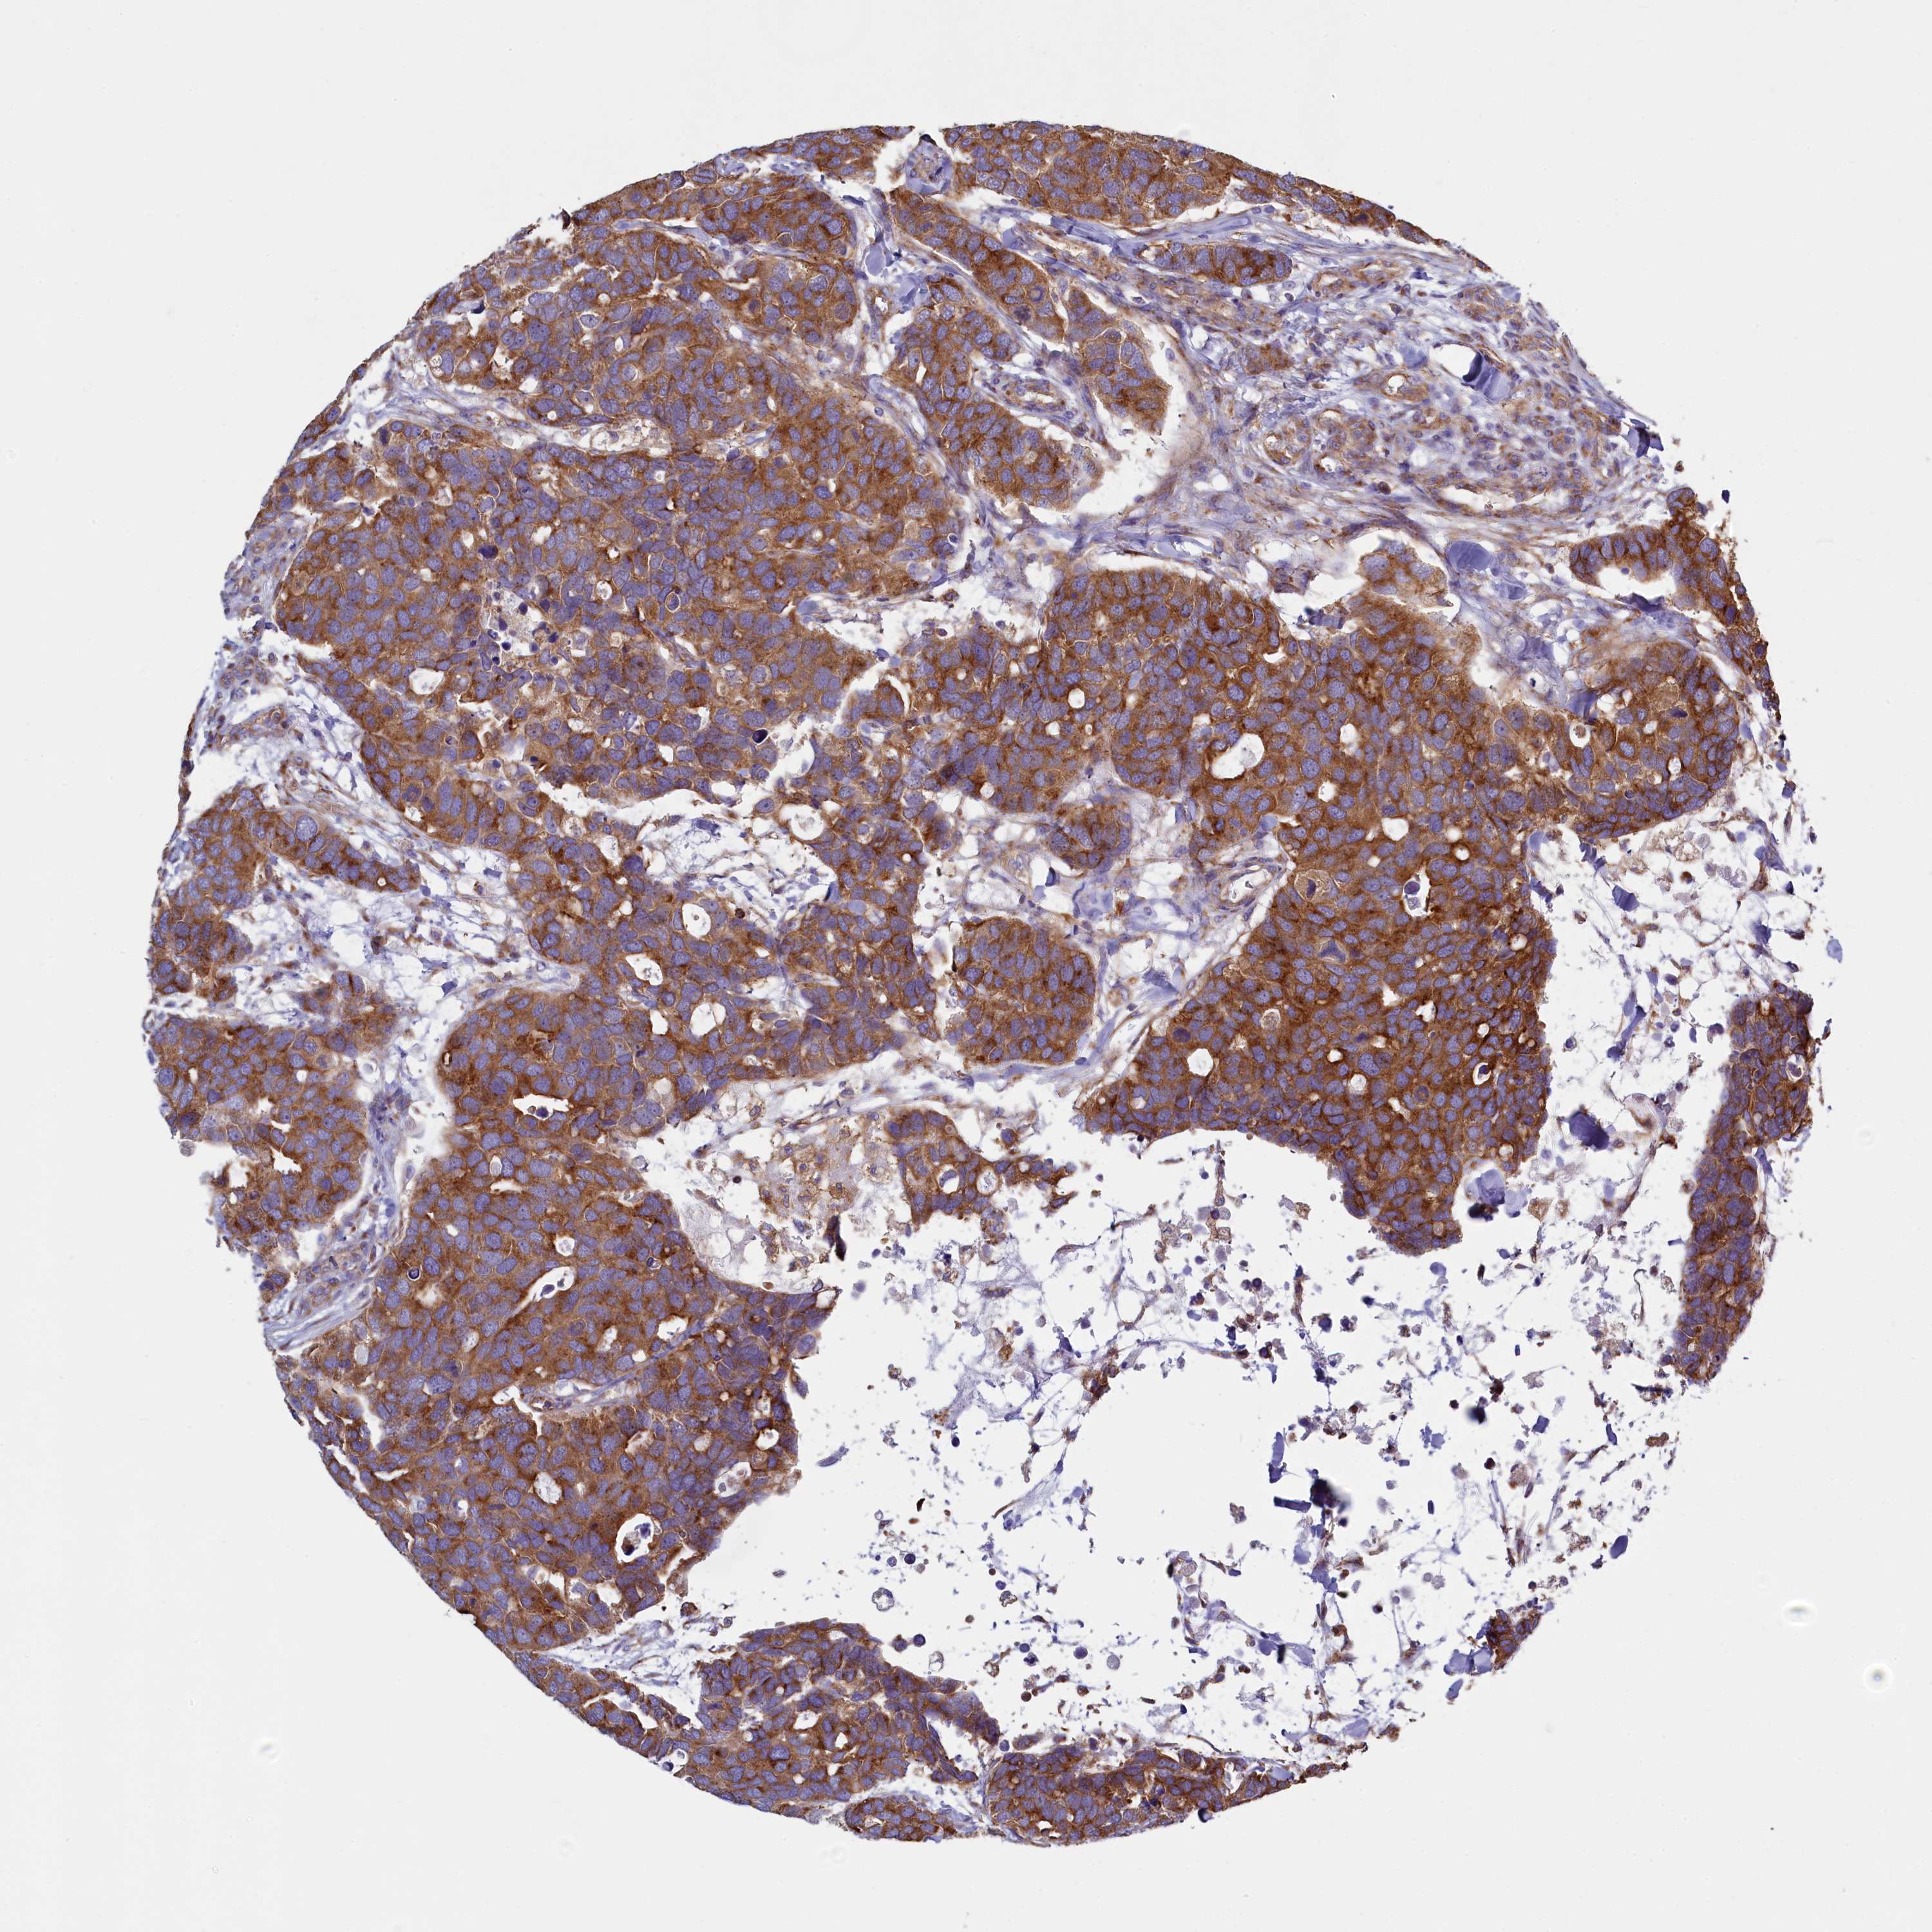

CANCER BREAST CANCER Show tissue menu

BRCA TCGA BRCA VALIDATION PROTEIN EXPRESSION